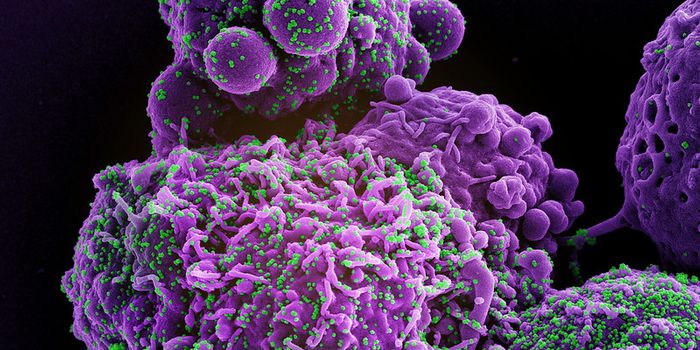

NOV 30, 2023CancerCytotoxic T cells (CTLs), a type of immune cells integral to fighting cancer, rely heavily on interaction with a molecul ...